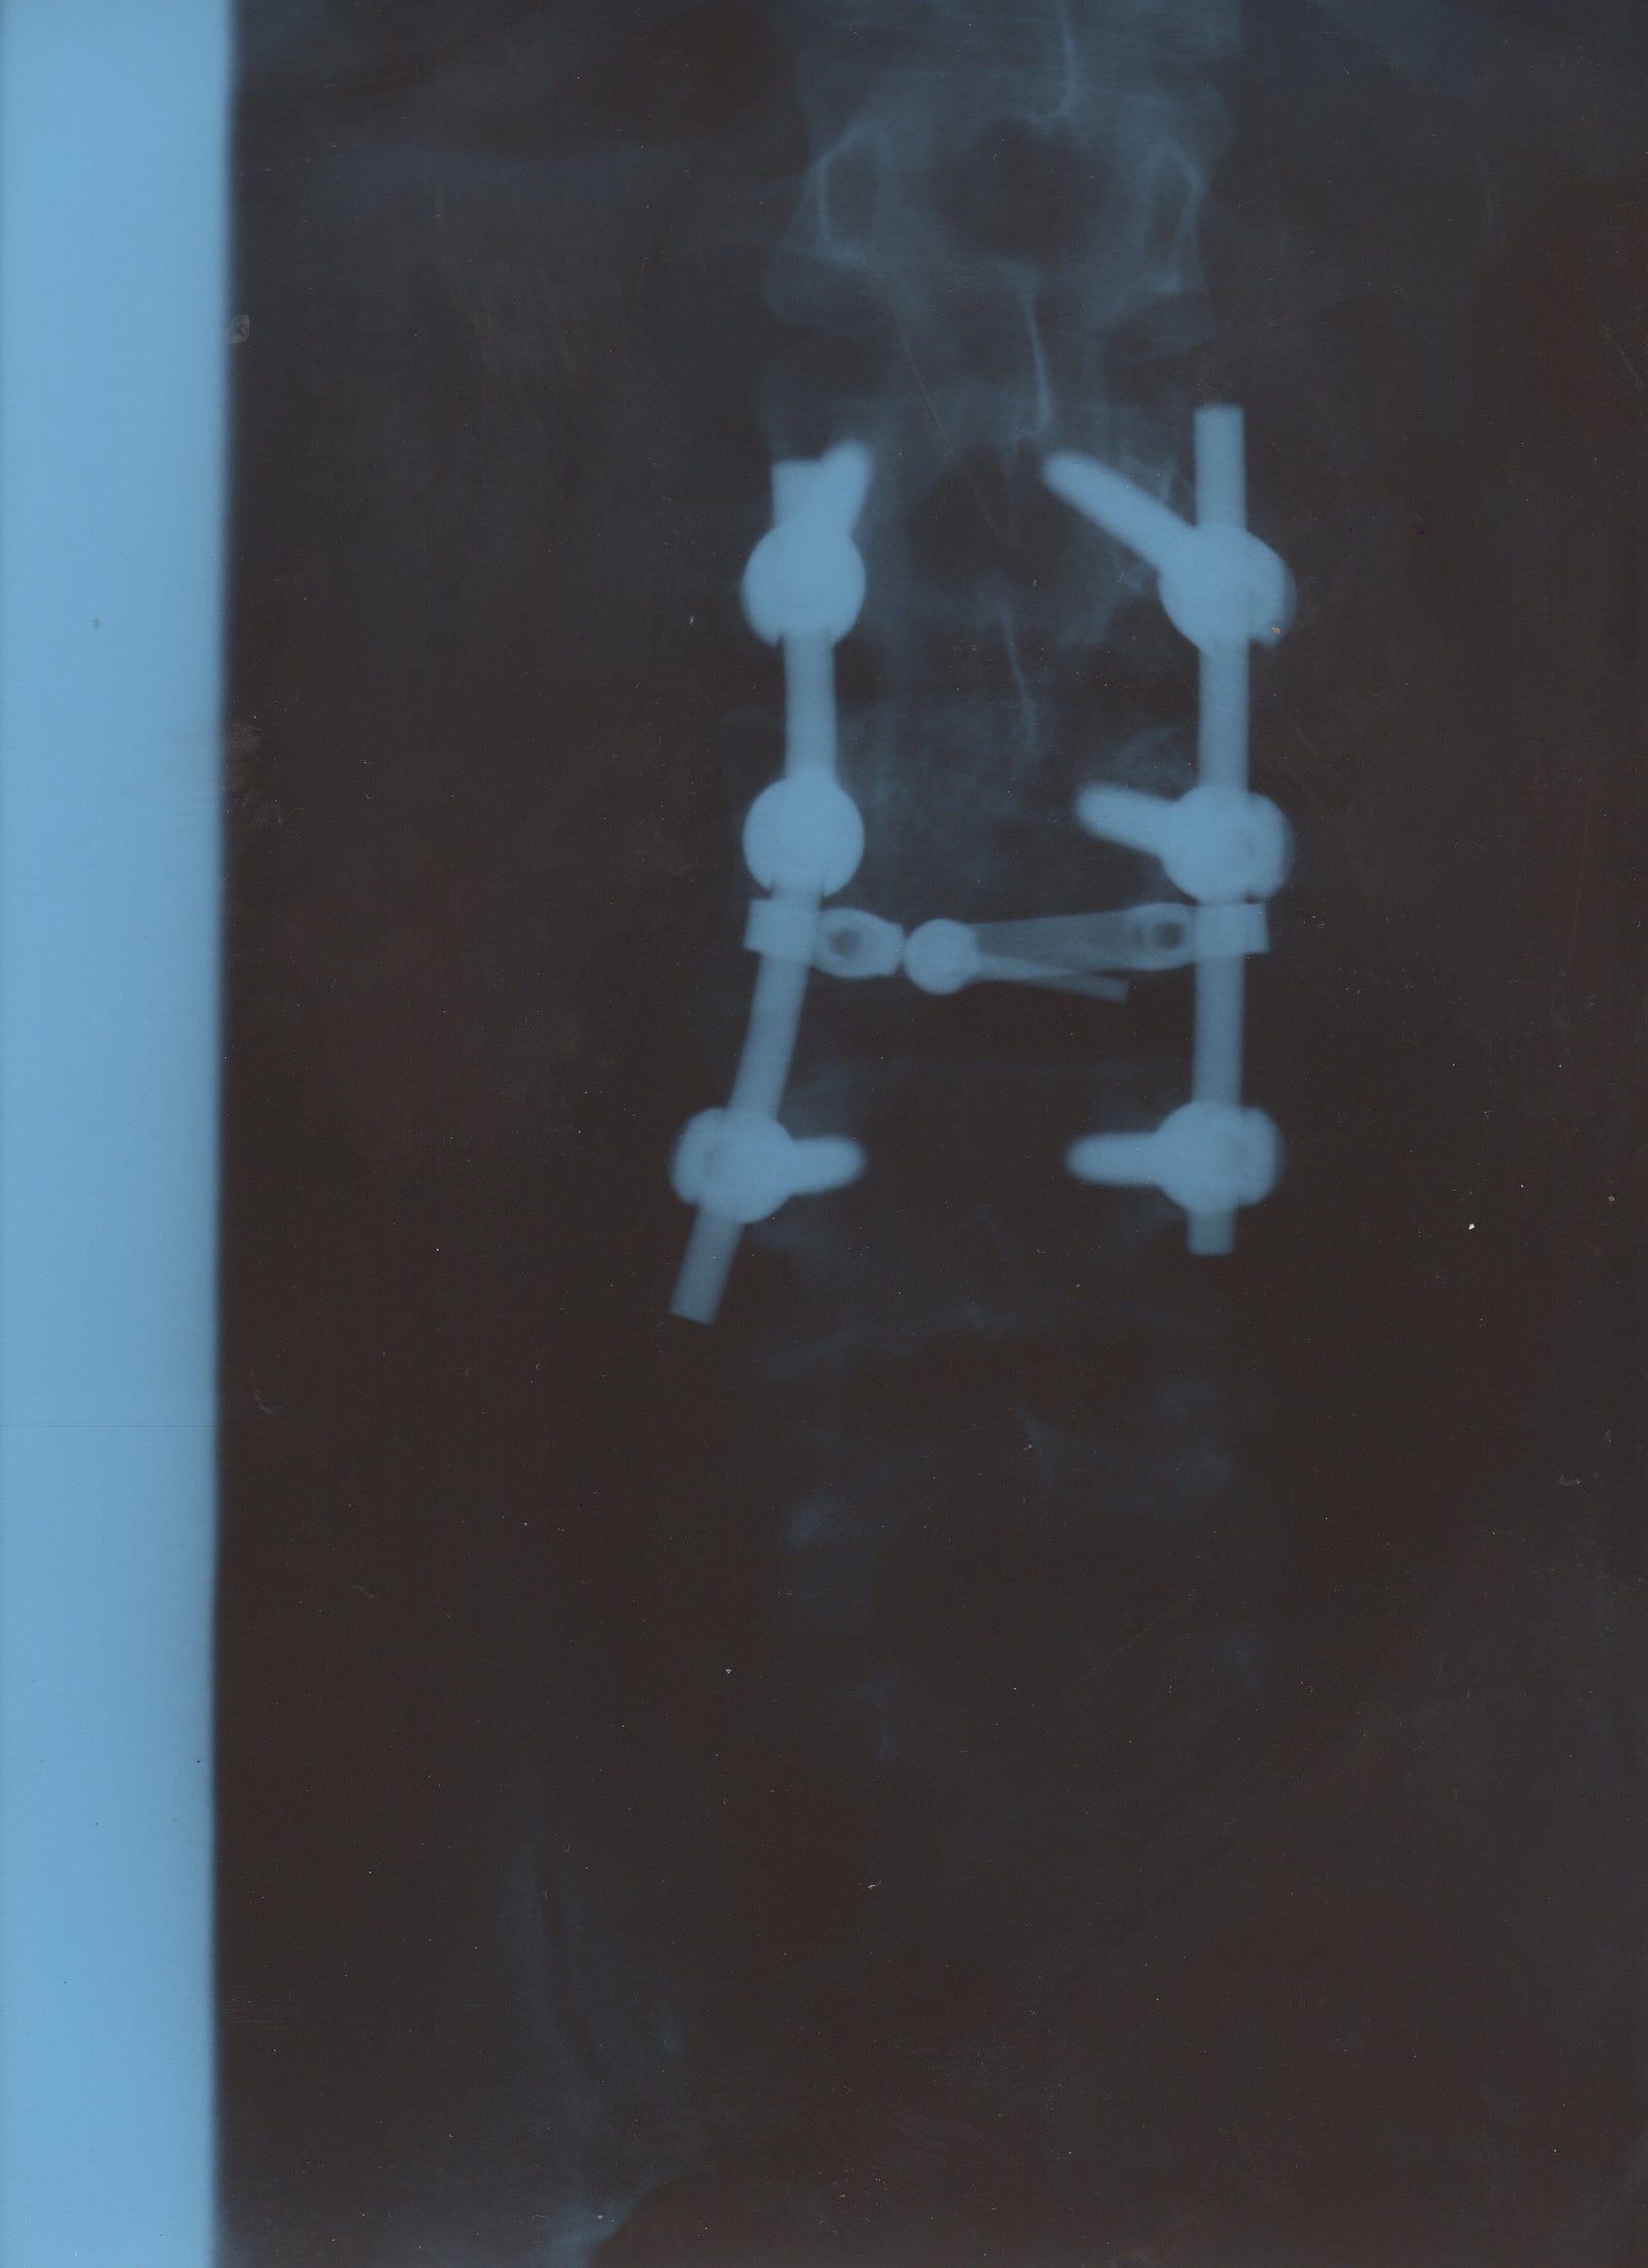

Having had three vertebrae fused about 20 years ago, laying down to sleep at night was nice. It felt good.